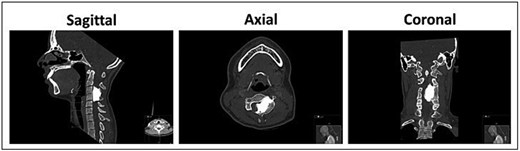

Magnetic resonance imaging (MRI) of the cervical spine demonstrated a hyperostotic lesion extending from C2 to C5. The lesion appeared predominantly intraosseous with periosteal extension but without involvement of adjacent soft tissues. There was significant left-sided spinal canal encroachment, resulting in severe cord compression (canal narrowing <5 mm). T2-weighted sequences showed deformation and signal changes within the spinal cord consistent with compressive myelopathy (Fig. 1). Complementary computed tomography (CT) revealed dense cortical hyperostosis with a characteristic “dripping candle wax” appearance (Fig. 2).

Pre-operative CT scan of the cervical spine demonstrating dense cortical hyperostotic lesion along the anterior and posterior elements of C3–C4 with classic “dripping candle wax” morphology, indicative of melorheostosis.